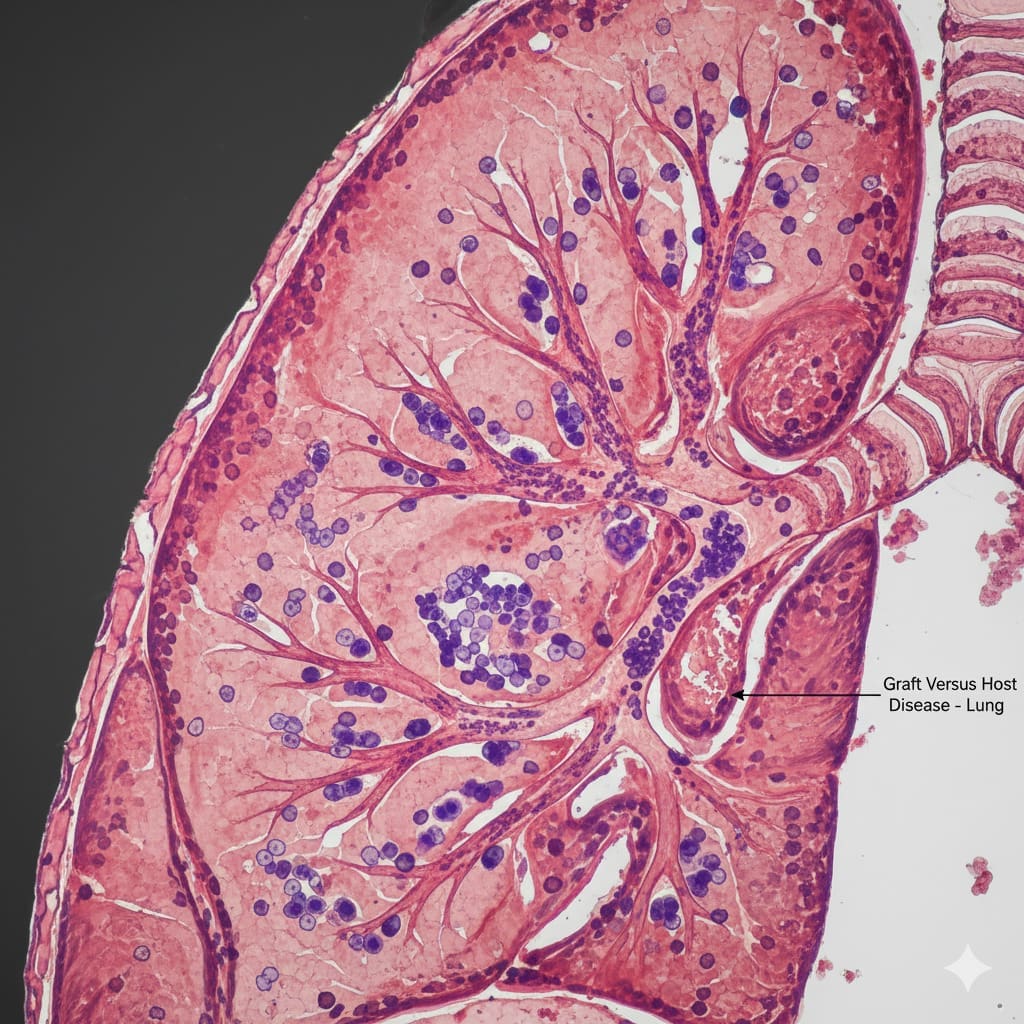

The Pathophysiology of Pulmonary GVHD

Pulmonary GVHD is a complex fight between donor immune cells and the host’s lung. This fight causes inflammation and damage to the lung. Knowing this helps us find better ways to diagnose and treat it.

Studies show T cells drive the GVHD immune response. When donor T cells see host antigens, they attack the host’s tissues, including the lungs.

Host vs. Graft Immunologic Interactions

The fight between the host and graft is at the heart of GVHD. Donor immune cells see the host’s tissues as foreign and attack. This can badly damage the lungs.

CD8+ CTLs and other immune cells play a big role in this fight. The table below shows the main interactions in pulmonary GVHD.